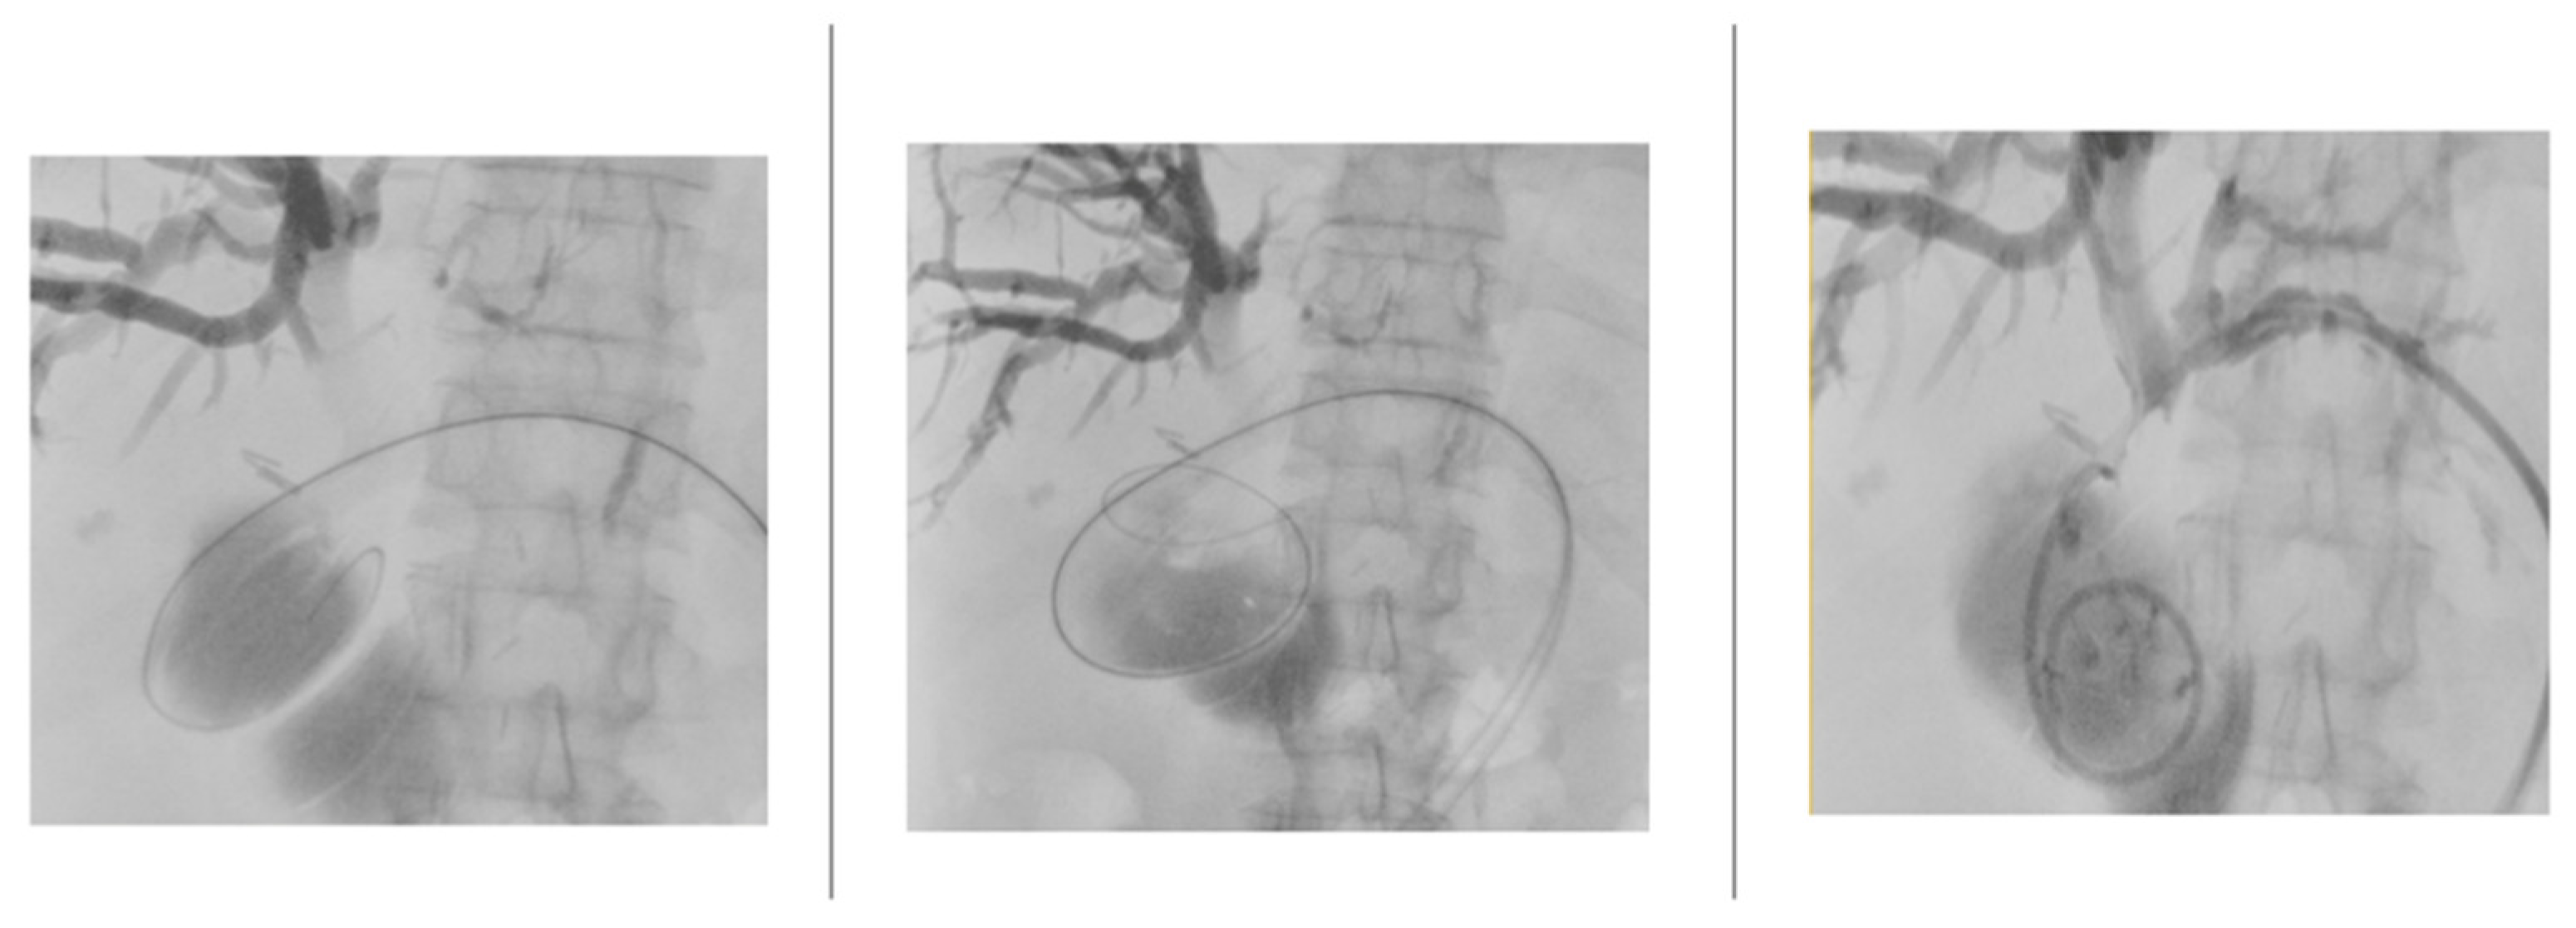

After fluoroscopic visualization of the biliary system, a .018” Cope Mandril Nitinol guidewire with platinum tip (Cook Medical) was inserted through the Chiba needle, followed by replacement with an introducer equipped on a tri-axial system to stabilize the access. Subsequently, the .018” guidewire was replaced by a standard-type 150 cm angled hydrophilic guidewire (Radifocus, Terumo) to cross the stenosis up to the duodenum. This guidewire was replaced by a .035” 145 cm Amplatz-type extra stiff guidewire, over which an 8/10/12 Fr internal-external biliary drainage catheter was positioned (Figure 4).

Figure 4. Images depicting the insertion of the guidewire up to the duodenum and the placement of the biliary drainage.